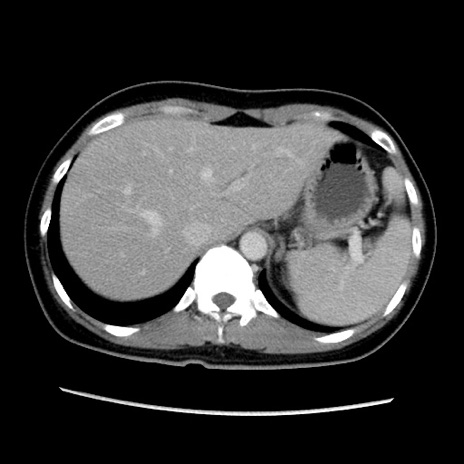

MRI(4日後)

【症例】40歳代女性

【主訴】上下腹部痛

【現病歴】2日目から下腹部痛あり。夜間は痛みで眠れなかった。昨日より上腹部痛と下痢が出現。臥位で痛みは軽快したため、休んでいた。本日になって臥位でも立位でも痛みが強くなってきたため救急要請。

【既往歴】子宮内膜症

【身体所見】部:平坦・軟、左上下腹部に圧痛あり、反跳痛あり。

【データ】WBC 21800、CRP 26.78